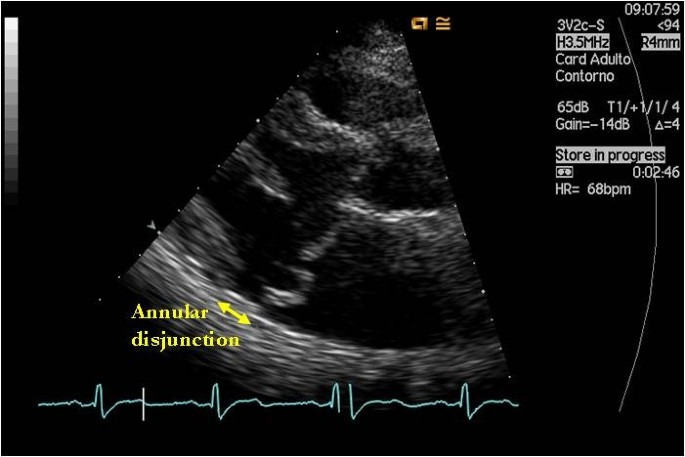

3.1.1. 표준 2차원 심장초음파: "How-To" 가이드

- 핵심 단면도(Key View): 우측 흉골 장축 단면도(Right Parasternal Long-Axis, PLAX) 4-chamber 및 5-chamber view가 가장 중요하다. 이탈은 전형적으로 후방(벽측) 소엽(posterior/mural leaflet)의 기저부에서 관찰된다.4

- 시점의 중요성: MAD는 수축기에 발생하는 현상이다. 판막 경첩과 심실 심근 사이의 분리는 좌심실이 가장 작아지는 수축기말(end-systole)에 최대로 나타나므로, 측정은 반드시 이 시점에서 이루어져야 한다. 이 틈은 이완기에는 종종 사라지거나 미미해진다.4

- 측정 기법: 측정은 좌심방벽에 부착된 후방 소엽의 삽입 지점에서부터 좌심실 심근의 꼭대기(crest)까지 수직으로 내린 직선 거리로 정의된다.4 이탈 거리를 측정할 때는 심장 주기에 따른 변화를 확인하기 위해 시네 루프(cine loop)를 면밀히 검토해야 한다.